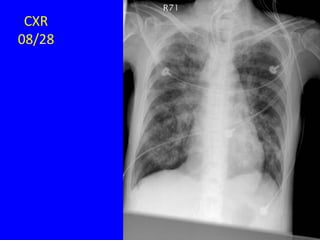

08/28

HRCT